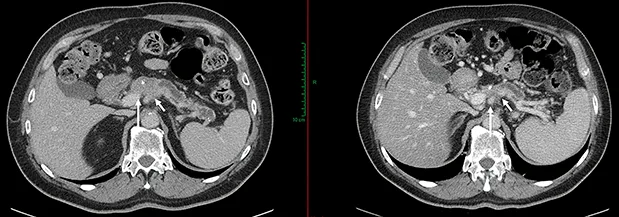

Figure 4 : AP localement avancé non résécable. Envahissement du TC > 180° et de l’AMS < 180°